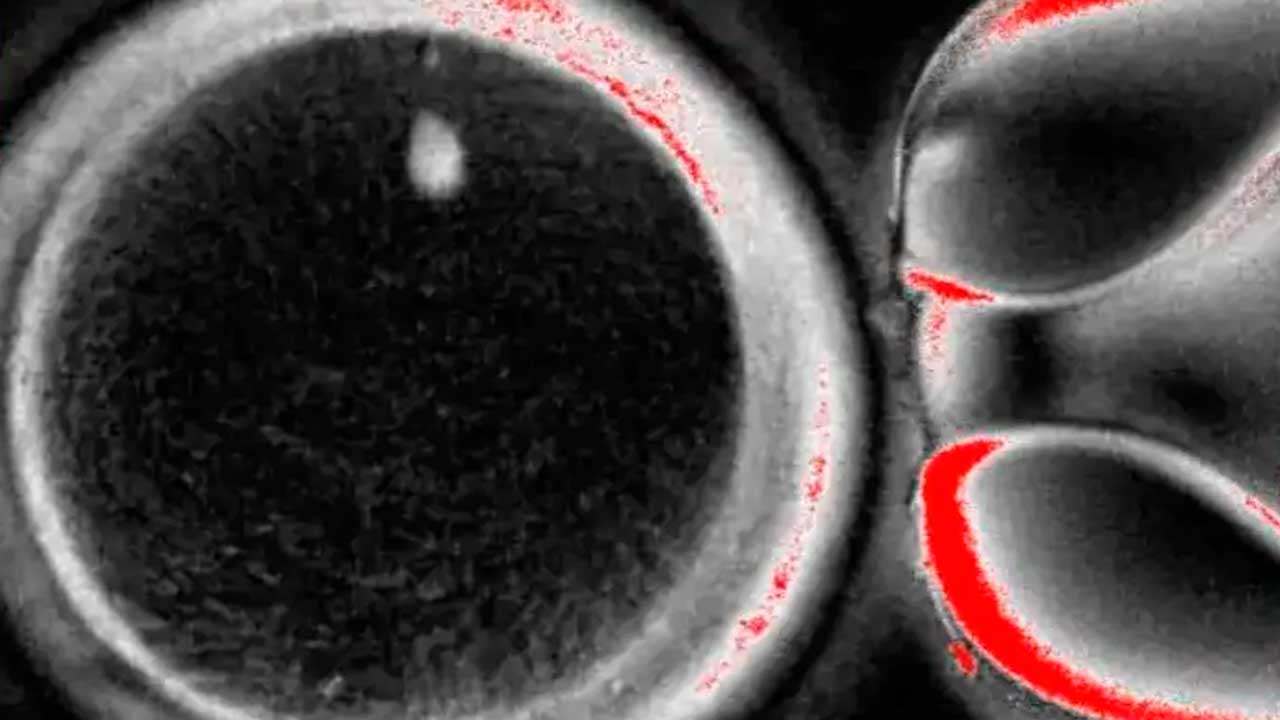

La investigación podría ser una respuesta a la infertilidad, que afecta a una de cada seis personas en el mundo. Foto cortesía del Laboratorio Mitalipov de la Universidad de Salud y Ciencias de Oregón

Crearon 82 ovocitos, que luego fueron fertilizados con esperma mediante fecundación in vitro (FIV).

Después de seis días, menos de 9 por ciento de los embriones se desarrollaron hasta el punto en que hipotéticamente podrían ser transferidos al útero en un proceso estándar de FIV.